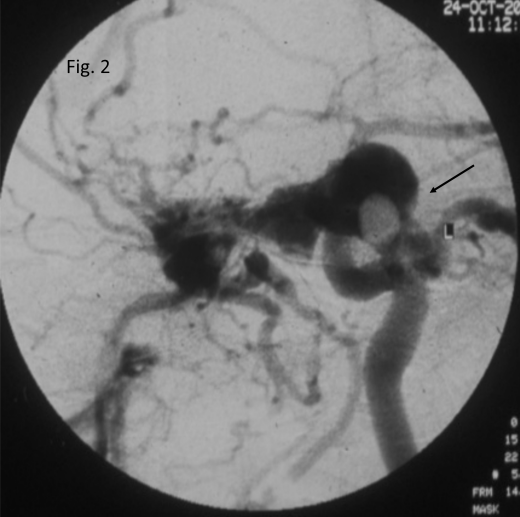

A thrill could be felt on both sides while a bruit was noted only on the left side on palpation and auscultation respectively. Based on the clinical signs and symptoms, an initial diagnosis of CCF with recent CRAO was made. Digital subtraction angiography (DSA) was subsequently ordered. 4-vessel DSA revealed a high flow CCF Barrow’s type A (Figure 2 [Fig. 2]). Given the nil visual prognosis but considerable cosmetic blemish he underwent an attempt of embolization of the fistula but it was unsuccessful.

Figure 2: Digital subtraction angiography, antero-posterior view, left sided. Pooling of contrast material in the cavernous sinus with a direct communication (arrow) between the internal carotid artery and the cavernous sinus is seen, suggestive of Barrow’s type A carotid cavernous fistula.